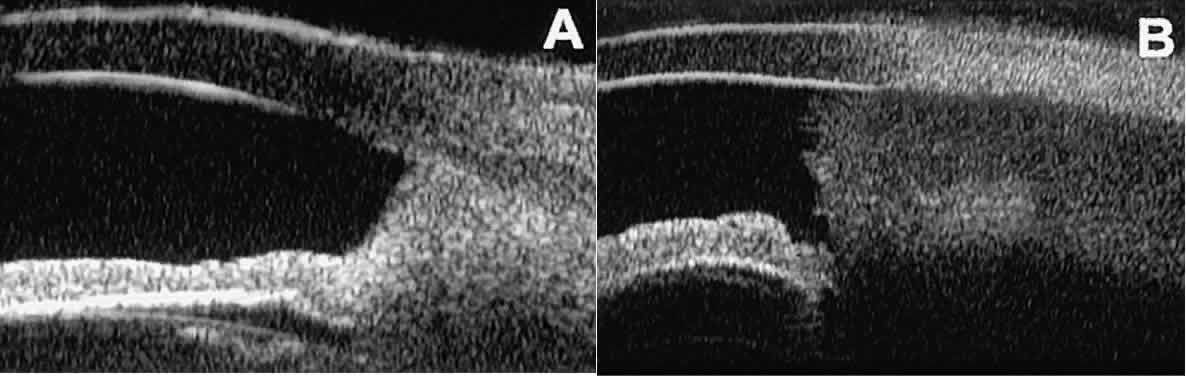

Cystic lesions of the iris and ciliary body can be of four types: primary neuroepithelial cysts, stratified squamous epithelial cysts, neuroepithelial cysts associated with solid tumors, and intratumoral cavities.15 Primary neuroepithelial cysts (see Fig. 22) are very distinct on UBM imaging. These lesions consist of a central sonolucent cavity surrounded by a thin wall of highly reflective neuroepithelial cells. They arise from the posterior surface of the iris (see Fig. 22A), in the iridociliary sulcus (see Fig. 22B and C), or from the inner aspect of the ciliary body (see Fig. 22D). They are often multifocal (see Fig. 22C and D) and bilateral.15 The largest lesions of this type typically occur in or near the horizontal meridians.

Stratified squamous epithelial cysts (Fig. 23) are almost exclusively unilateral and unifocal,15 have substantially thicker walls than do primary neuroepithelial cysts, and usually contain prominent intracavitary particles (desquamated epithelial cells). Almost all such cysts involve the peripheral iris and angle region. Such cysts are usually secondary to prior ocular surgery or laceration in which conjunctival epithelial cells were implanted into the iris stroma.

Fig. 23. UBM features of stratified squamous epithelial cysts of iris. A. Thick-walled implantation cyst of stratified squamous epithelium replacing normal iris. Note intracavitary particles. B. Bilobed stratified squamous epithelial inclusion cyst of iris with prominent intracavitary particles.

Secondary neuroepithelial cysts occur rather frequently in association with solid tumors of the iris or ciliary body.15 On UBM (Fig. 24), such cysts appear quite similar to the primary neuroepithelial cysts described above; however, they are associated with a solid mass arising within the iris or ciliary body.

Fig. 24. UBM appearance of neuroepithelial cysts associated with solid tumors of the iris and ciliary body. A. Single neuroepithelial cyst associated with iris melanoma. B. Multiple neuroepithelial cysts associated with iridociliary melanoma.